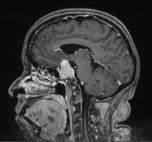

La tiroides es una glándula que pertenece al sistema endocrino; se encuentra en la cara anterior del cuello y tiene la forma de una mariposa.Esreguladaporlaglándulahipófisis,la cual produce TSH (hormona estimulante de tiroides) enviando la señal para que la glándula tiroideslibereprincipalmentehormonastiroideas: T4 (tiroxina) y T3 (triyodotironina), que tienen diversas funciones vitales en el organismo, ya queintervienenenlaregulacióndelmetabolismo y la temperatura corporal; el crecimiento; desarrollodelsistemanerviosoycontroldelritmo cardiaco;pesoyfertilidad.

Elmejormétodoparaevaluarloseselultrasonido, enelcualesimportantequeelespecialistadefina algunas características como el tamaño, la forma, el contenido (quístico, sólido o mixto), entre otras variables, para decidir si se realiza o no, una puncióndelnódulo(BAAF),adescartarcáncerde tiroides.Afortunadamente,lamayoríadeellosson benignosyúnicamenterequierenseguimientocon ultrasonido.